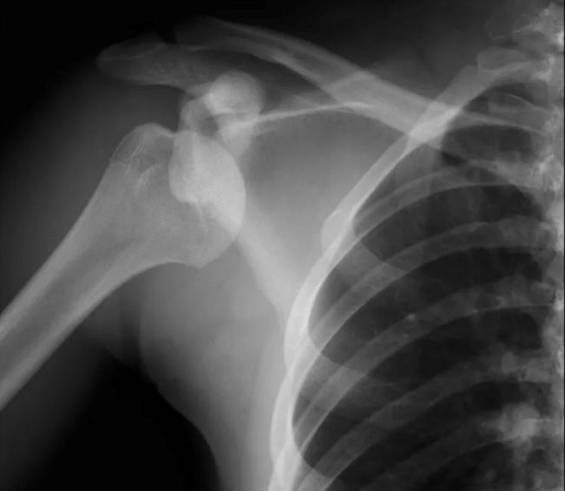

肩關節脫臼(見圖一)是最常見的關節內創傷,多數由運動時的激烈碰撞所引致。患者受傷後會出現極度疼痛、肩膀變型、腫脹,以及完全不能活動肩膀及手臂等症狀。如懷疑肩膀脫臼,千萬不要自行嘗試復位,因為有機會導致骨折或傷及肩膀周邊的神經線。傷者應先立刻停止運動並休息,使用三角巾暫時固定傷肢,並儘快求醫,經X光檢查後再由醫護人員進行復位。